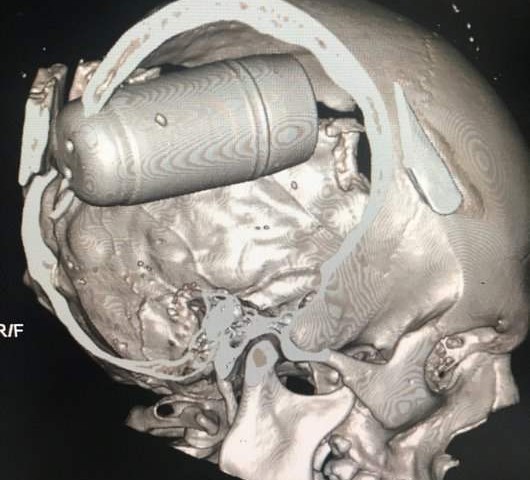

La forza prodotta ha colpito le vittime in maniera orribile: granate intere (come si vede nel dettaglio di una Rx in alto) o grandi schegge di metallo sono penetrate nel cranio e nei corpi dei manifestanti, dalle cui ferite aperte usciva ancora del fumo. Gli esperti di Amnesty International hanno detto che quelle immagini sono tra le peggiori mai viste.